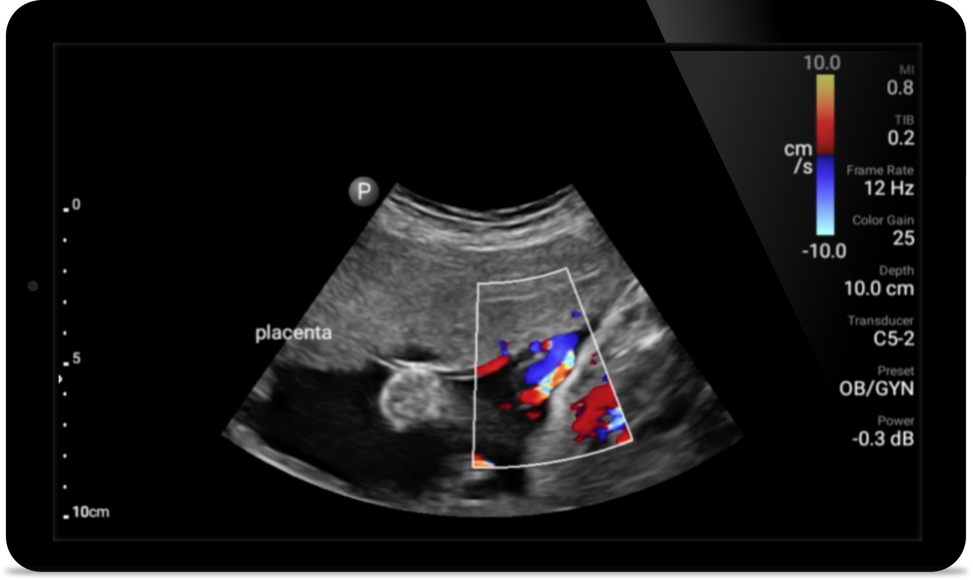

Vroegtijdige detectie kan helpen voorkomen dat aandoeningen levens-bedreigend worden

Lumify kan helpen de subtiele details van een beeld zichtbaar te maken en afwijkende weefselstructuren bloot te leggen vanuit verschillende hoeken. Hierdoor kunt u met vertrouwen realtime beslissingen nemen, van diagnose tot herstel.